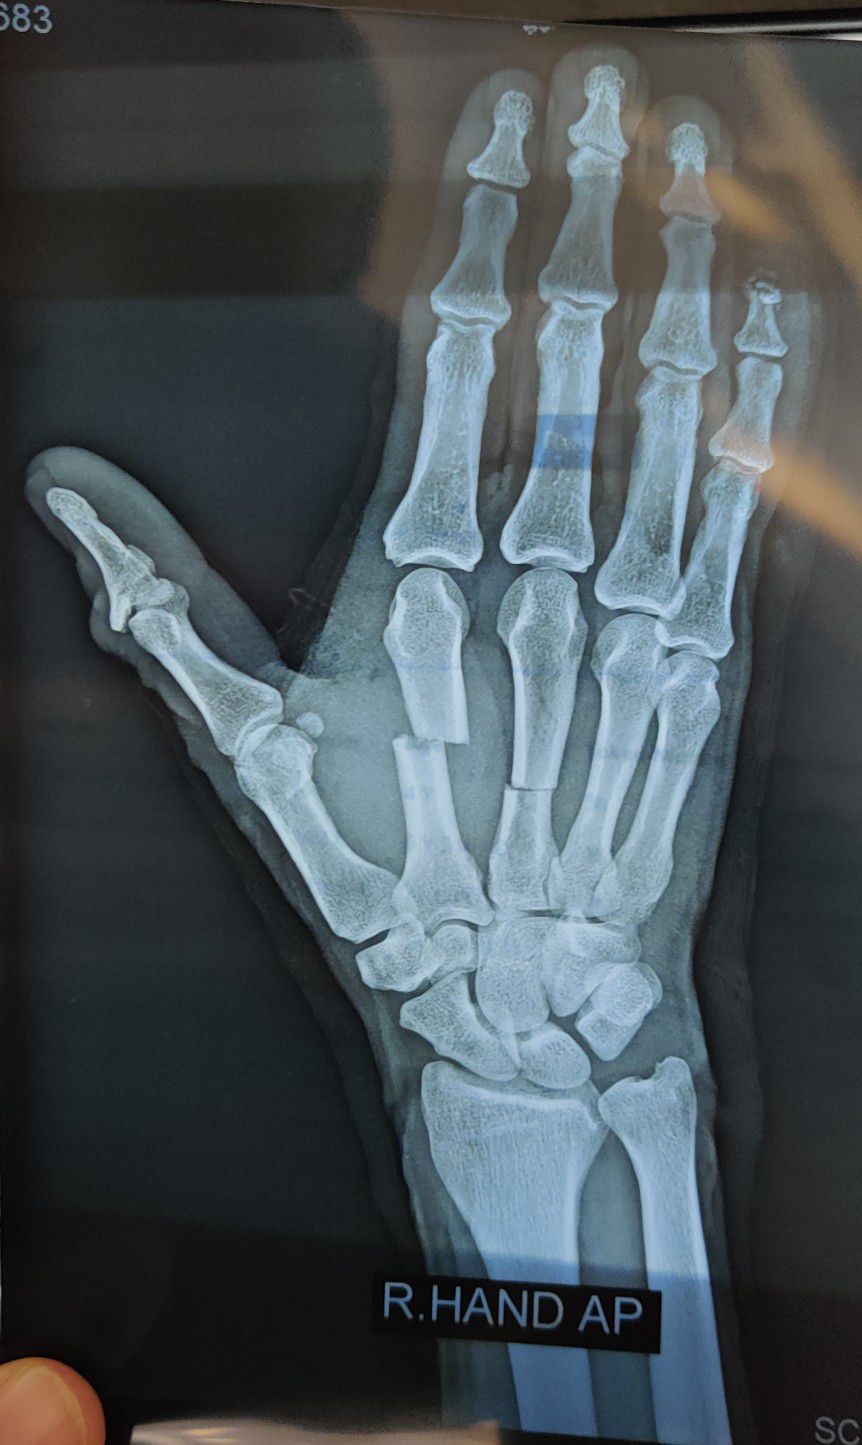

Sharp cut and fracture 2nd & 3rd metacarpal

Fracture

Rta

Metacarpal